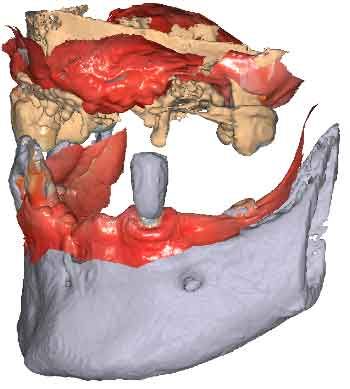

Lorsque les scans IOS traditionnels manquent de références nécessaires, les données du CBCT peuvent servir d'alternative viable. En utilisant les fichiers du CBCT, le clinicien peut établir des références anatomiques précises pour la planification du traitement.

Pour pouvoir utiliser les données CBCT comme modèles initiaux, nous devons transformer le fichier DICOM en un fichier STL. Découvrez-en plus sur la segmentation CBCT et son utilisation dans TWIM ci-dessous.

Avant d'acquérir le CBCT, j'ai ajouté 2 morceaux de composite à la mandibule pour pouvoir effectuer le processus de picking pendant le protocole MODJAW. Il s'agit d'une astuce utile à retenir en cas d'absence de dents.

En important les fichiers DICOM du patient au lieu des scans IOS, les cliniciens peuvent enregistrer le mouvement de la mâchoire, facilitant ainsi la planification précise du traitement.

Importez les modèles CBCT segmentés en tant que modèles initiaux dans TWIM

Sélectionnez 4 points virtuels sur la mandibule du modèle osseux importé